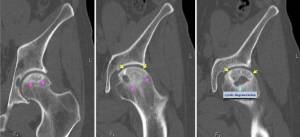

Выявить диагноз на ранних стадиях можно только при помощи компьютерной или магнитно-резонансной томографии. Если же «стаж болезни» превысил год, а то и более, только тогда с помощью рентгеновского исследования можно выявить точный диагноз. Ультразвуковое исследование делать бесполезно для диагностики заболевания.

3 стадия (секвестрации) — головка становится более плоской, теряет нормальные контуры. Суставная щель продолжает расширяться. На снимках визуализируются отдельные фрагменты кости различного размера и формы, не имеющие нормальной структуры. Определяется утолщение и укорочение шейки бедра.